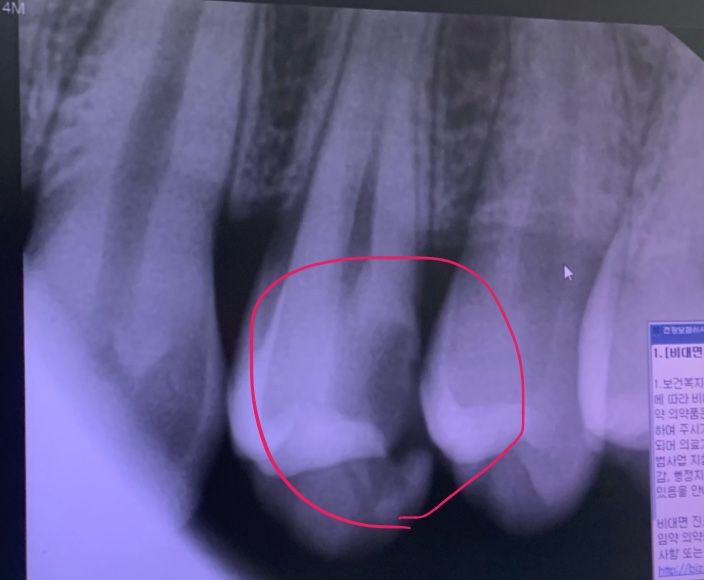

치과에서 신경치료 진단을 받았습니다!

치아에 구멍이 났다고 하더라구요 ㅠㅠ

이게 깨져서 음식물이 들어가서 썩은건지, 썩어서 깨진건지는 잘 모르겠지만

아무튼 치과에 가서 진단을 받았더니 신경치료를 권해서 치료를 받아야할 것 같습니다.

1. 저정도로 충치가 진행된 치아는 신경치료말고 답이 없는 수준일까요?

2. 이미 저정도로 충치가 진행된 치아는 최대한 빨리 치료받는게 낫나요? 한달정도 기다려야할거같은데.. 금전도 그렇고 ㅠ.ㅠ 최대한 양치 꼼꼼히 + 가글 하면서 관리하면 조금 괜찮을까요?

3. 견적을 지르코니아로 70만원 정도 잡았거든요 신경치료 + 지르코니아 크라운(?) 괜찮은 견적인가용?

신경치료를 하셔야될것같습니다. 충치가 많이 진행됫네요. 보통 신경치료 비용에 기둥비용 크라운 비용하면 그정도는 견적이 나올거 같습니다.

신경치료 해야하는 치아입니다. 빨리 치료 받으시는 것이 좋겠고 가격도 평범한 수준입니다.